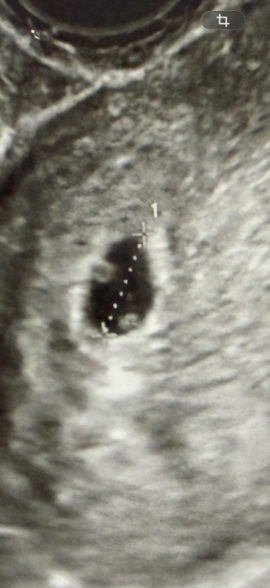

先日、受診した際にエコーを撮った際のエコーなのですが胎嚢1つに対して胎芽?なのか2つ丸いのが写っていて、もしかしたら一卵性の双子なのか?と診察後改めてエコー写真を見返した際に疑問に思いました。

画像だけで「双子かどうか」を断定するのはできないのですが、見えている範囲だと、ママさんがおっしゃるように、何が小さなものが、2つあるようには見えますね。

ですが、これが胎嚢といった確証を申し上げるのは難しいです。

ただし、まだ週数が早く、予定日などが確定できない場合に、見え方に個人差がかなりありますし、エコーの角度によっても、紛らわしくなることがあります。最終判断は次回のエコーでの確認が確実です。